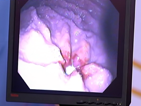

[IMG]med23.png2017-04-25 05:39 23K